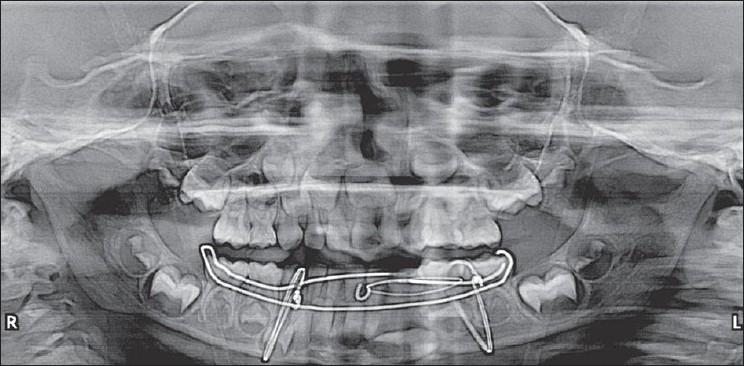

Mandibular fractures are relatively less frequent in children when compared to adults, which may be due to the child's protected anatomic features and infrequent exposure of children to alcohol related traffic accidents. Treatment principles of mandibular fractures differ from that of adults due to concerns regarding mandibular growth and development of dentition. A case of a 4.5-year-old boy with fractured body of mandible managed by closed reduction using open occlusal acrylic splint and circum mandibular wiring is presented. This article also provides a review of literature regarding the management of mandibular body fracture in young children.